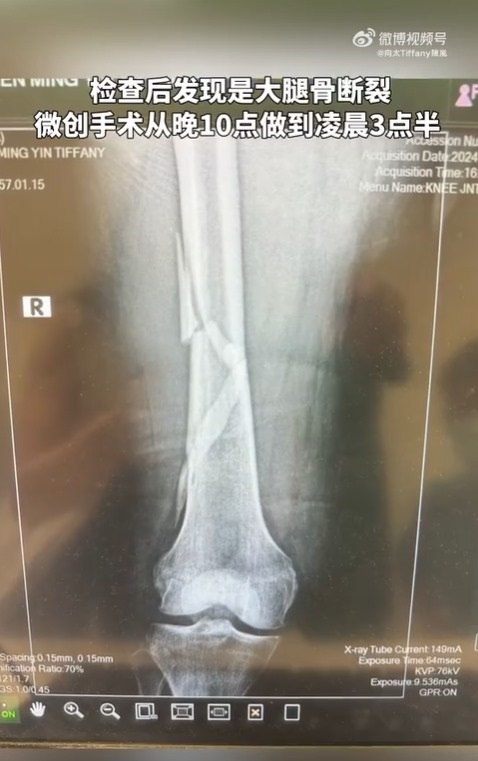

最近向太在家中浴室洗澡時,因踩在沒有防滑墊的地方而不慎滑倒,還痛到站不出來,而且由於門是關著的,所以叫了30分鐘才有人聽到,其後又因救護車的聲音會引起報道和不實猜測,因此沒有馬上叫救護車,整晚在浴室沒有郁動,到了第二天早上才叫私人醫生,最終由救護車送院,過程中老公向華強一直在她旁邊守護她。入院檢查後發現大腿骨斷裂,做了5個半小時的微創手術,目前需在家持續復健訓練。